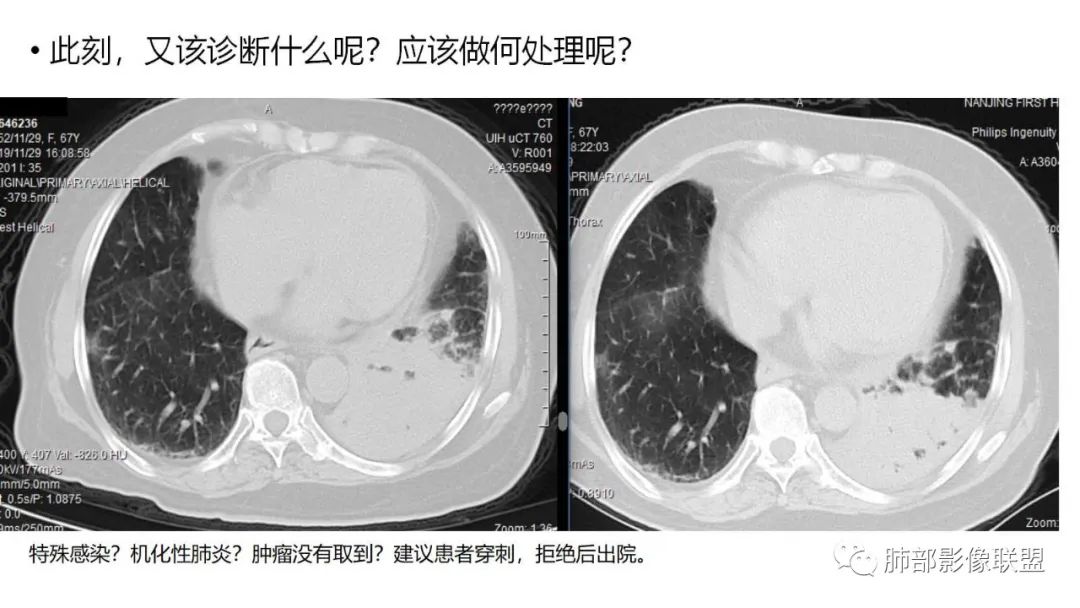

2.粘液腺癌易伪装成肺炎的形态,尤其是当患者本身具有免疫色彩的时候,易误诊为间质性肺炎,或肺部感染。若治疗无效,取得病理很重要。

3.粘液腺癌常常因为标本不够,病理无法诊断,影像诊断很重要,取病理方案很重要。甚至多次取病理。

4.回到本例,左下肺病变两次好转,均未经过肿瘤治疗,第一次是支气管镜后,第二次是当其他病变都在进展的情况下,左下肺病变范围反而缩小趋于浅淡。